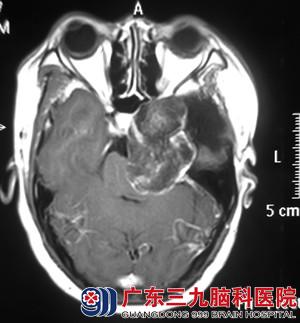

芳姐十二年前被诊断为“颅内胆脂瘤”,在当地医院行手术治疗,但术后遗留下左侧面部麻木、左侧眼球外展障碍,视物重影及左下肢运动欠佳。去年8月开始出现发作性左侧面部、眼睑抽搐,一周前加重,到我院行头颅MR提示:左侧中后颅窝占位性病变,考虑胆脂瘤复发。

当看到检查结果时,芳姐一股恐惧感油然而生,经再三考虑决定在三九脑科医院接受手术治疗。入院时查体:患者左侧眼球结膜稍充血,外视及上视障碍,左侧面部麻木,左侧面部肌肉萎缩。完善相关检查后,由综合神经外科的鲁明主任主刀,在全麻下行硬脑膜外入路左侧中后颅窝复发胆脂瘤切除术,术中显微镜下见黄白色肿瘤组织,质地疏松,无血供,考虑为胆脂瘤复发,予肿瘤切除,修补颅底,手术顺利结束。术后芳姐经过专科治疗,术前症状均明显较术前好转,十天后芳姐康复出院。术后病理结果:胆脂瘤。

术前 ?xml:namespace>